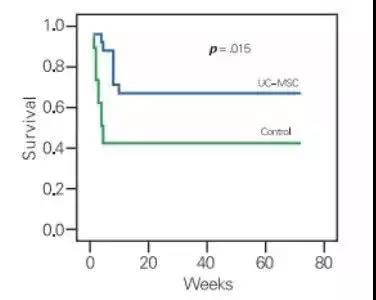

延长患者寿命

研究显示:干细胞治疗可显著提高肝病患者的生存期。